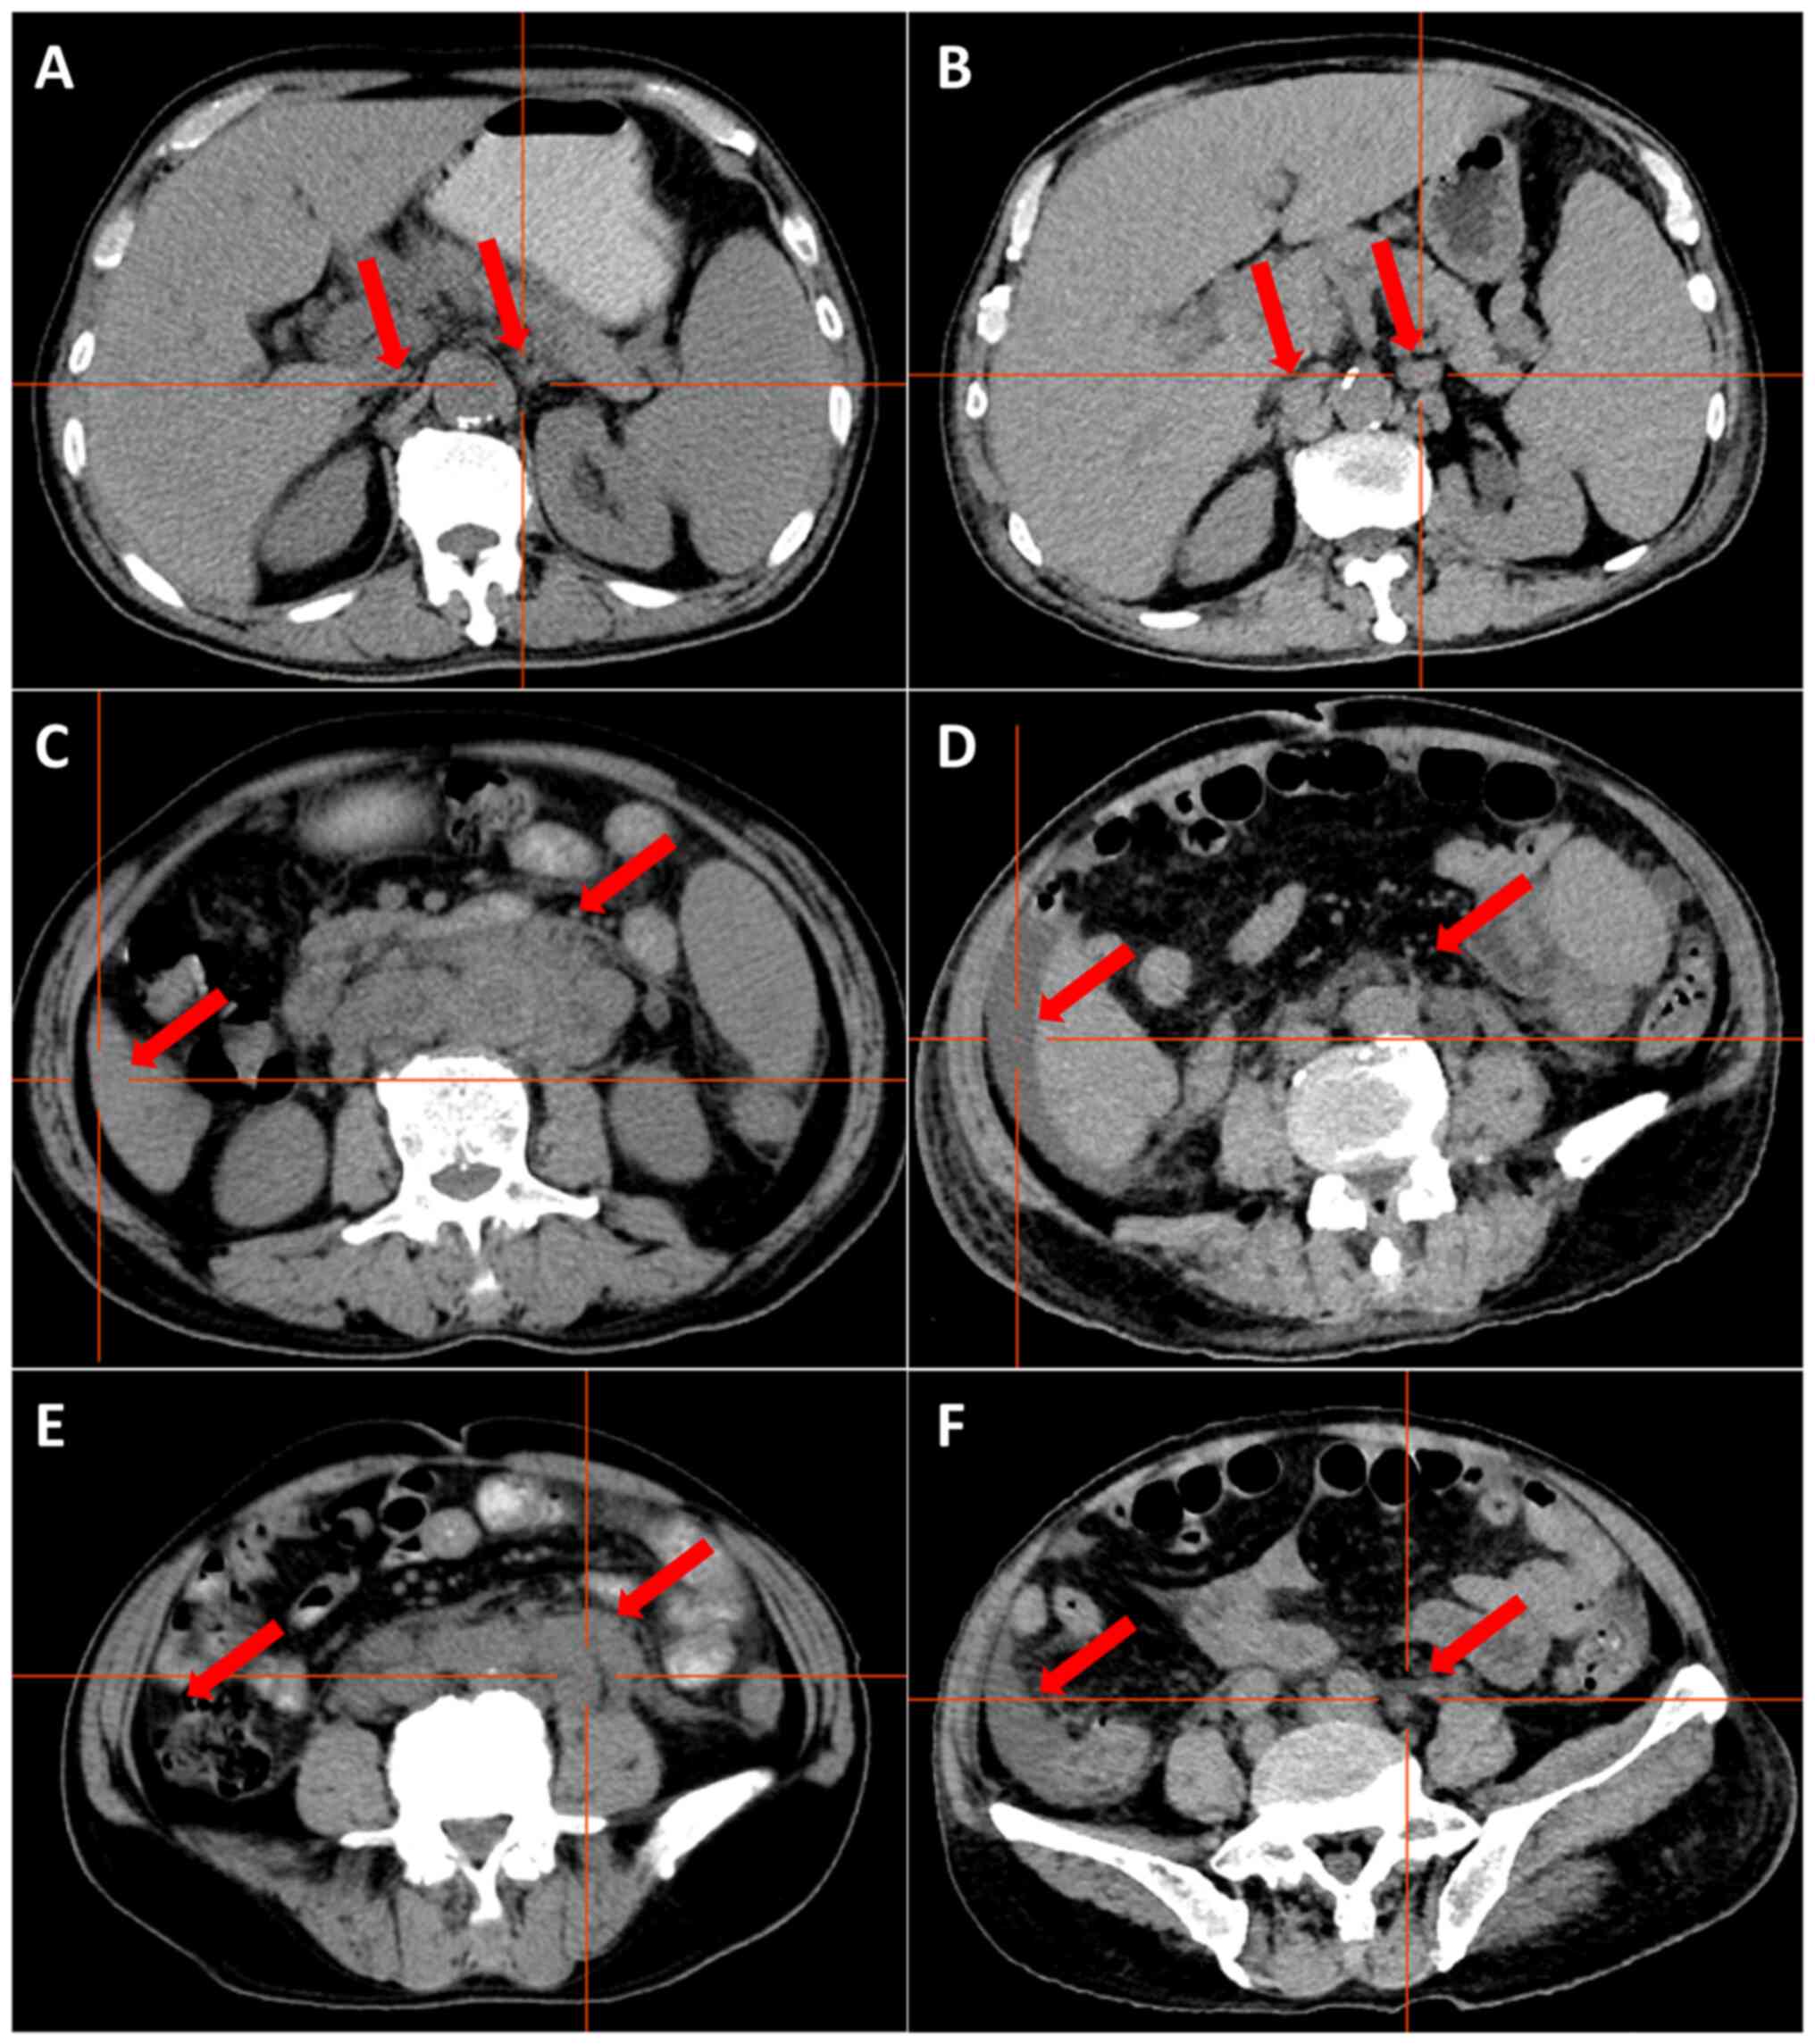

Figure 4.

Computed tomography images at first vs. second admission. Lymph nodes behind the pancreas (A) before and (B) after treatment, highlighted by red arrows; no lymph nodes were seen on either side of the abdominal aorta before treatment, and ~6 lymph nodes with a maximum size of 16×8 mm appeared on both sides of the abdominal aorta after treatment. Lymph nodes around the abdominal aorta and retroperitoneum (C) before and (D) after treatment, highlighted by red arrows. Before treatment, there were numerous enlarged lymph nodes adjacent to the retroperitoneal abdominal aorta, some of which were fused to each other, making it difficult to determine the exact number of lymph nodes, the largest of which was 30×20 mm in size. After treatment, the lymph nodes were significantly reduced and some of them had subsided. Ascites (E) before and (F) after treatment, highlighted by red arrows. No ascites was seen before the treatment. Ascites appeared after the treatment.

Laboratory assessment results at admission and after one course of VA regimen (venetoclax 100 mg, D1; 200 mg, D2-28; azacytidine 0.1 g subcutaneously, D1-7) are presented in Table I. White blood cells, lymphocytes, cytokines interleukin (IL)-6 and IL-10 markedly decreased after treatment compared with before, but C-reactive protein levels were increased. Next-generation sequencing of peripheral blood, which assessed the protein-coding regions of 267 genes strongly associated with hematological disorders, revealed multiple mutations, including exosome complex exonuclease RRP44 (DIS3; 13q22.1), NRAS (1p13.2), TET2 (4q24), CUB and Sushi multiple domains 1 (CSMD1; 8p23.2), B-cell lymphoma (BCL)6 corepressor-like protein 1 (Xq26.1) and platelet-derived growth factor receptor (PDGFR)A (4q12) mutations (Table II). However, no mutations were found in the FMS-related receptor tyrosine kinase 3 (FLT3), JAK2, STAT, calreticulin (CALR) or MPL proto-oncogene thrombopoietin receptor (MPL) genes. Bone marrow cell classification showed that the proportion of lymphocytes was notably increased, and atypical lymphocytes were easily seen (73.5%) (Fig. 2A). Bone marrow tissue biopsies showed highly active myelodysplasia (60–70%) and reticular fiber staining was grade 2 (Fig. 2B-T) (21). Immunohistochemistry of cutaneous, lymph node and bone marrow tissue biopsies supported a diagnosis of a BPDCN (Figs. 1F-K, 2 and 3). Immunohistochemical examination of the bone marrow and lymph nodes was positive for TET2, NF-κB, NRAS and phospho (p)-ERK, and negative for PDGFRA, IL-6, IL-10, JAK2, STAT3 and TGF-β1. Flow cytometry analysis of the bone marrow showed abnormal cells, with 54.61% (Fig. S1B) expressing CD56 (Fig. S1K), CD45RA (Fig. S2A), CD2 (Fig. S2B), CD303 (Fig. S3D), human leukocyte antigen DR (Fig. S3E) and CD36 (Fig. S4B), partially expressing CD4 (Fig. S2C), CD103 (Fig. S2D), CD10 (Fig. S2E) and CD123 (Fig. S4A), weakly expressing CD7 (Fig. S2F), TCL1 (Fig. S4C) and T-cell restricted intracellular antigen 1 (Fig. S4D), and lacking expression of other myeloid or lymphoid markers. Additional detailed results of flow cytometry are shown in Fig. S1, Fig. S2, Fig. S3, Fig. S4, Fig. S5, Fig. S6, Fig. S7. CT demonstrated multiple enlarged lymph nodes above and below the transverse septum and splenomegaly with slight hypermetabolism. The largest retroperitoneal para-abdominal aortic lymph node was 30×20 mm (Fig. 4A, C and E). On the basis of these findings, the patient was diagnosed with BPDCN complicated by MF. The patient received a course of VA regimen (venetoclax 100 mg, D1; 200 mg, D2-28; azacytidine 0.1 g subcutaneously, D1-7). On day 6 of chemotherapy, the skin lesions had almost subsided (Fig. 1D and E) and the lymphocyte count had gradually decreased during this treatment period (Table III). On day 10 of chemotherapy, the patient was discharged.